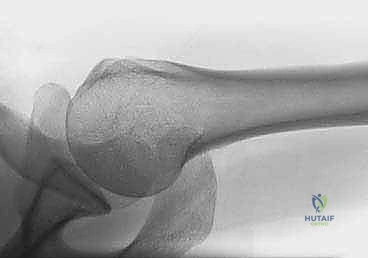

1. الرأس المفصلي (Articular Head): الجزء الكروي الذي يتمفصل مع التجويف العنابي للوح الكتف.

الخطر الأكبر في كسور هذه المنطقة هو تأثر التروية الدموية (الإمداد الدموي). الشرايين التي تغذي رأس عظم العضد دقيقة جداً وأي تمزق فيها قد يؤدي إلى حالة خطيرة تُعرف باسم "النخر اللاوعائي" (موت أنسجة العظام بسبب نقص الدم). وهنا تبرز عبقرية تقنية التثبيت عبر الجلد التي تحافظ على هذه الأوعية الدموية الحساسة.

2. الحفاظ على التروية الدموية: الجراحة المفتوحة تتطلب إبعاد العضلات والأنسجة عن العظم، مما قد يدمر الأوعية الدموية الدقيقة ويؤدي إلى نخر رأس العضد. التثبيت عبر الجلد يحافظ على هذا الغلاف الحيوي تماماً.